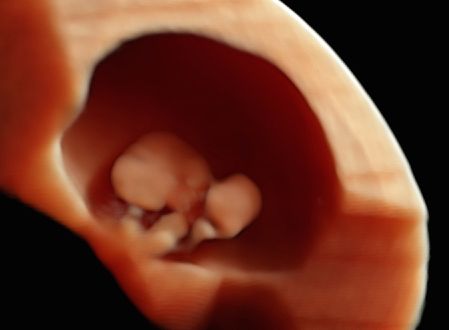

Credo che la Fertilità delle Pazienti e l'evoluzione fisiologica della GRAVIDANZA possano migliorare con una valutazione attenta della paziente PRECONCEZIONALE.

Credo che una corretta valutazione della GRAVIDANZA INIZIALE possa migliorarne il decorso e gli esiti.

• Gravidanza

Un viaggio davvero meraviglioso… alla scoperta del mio bambino. Dettagliata, minuziosa una visita davvero eccezionale! Ho visto davvero tutto del mio bimbo, bellissimo!